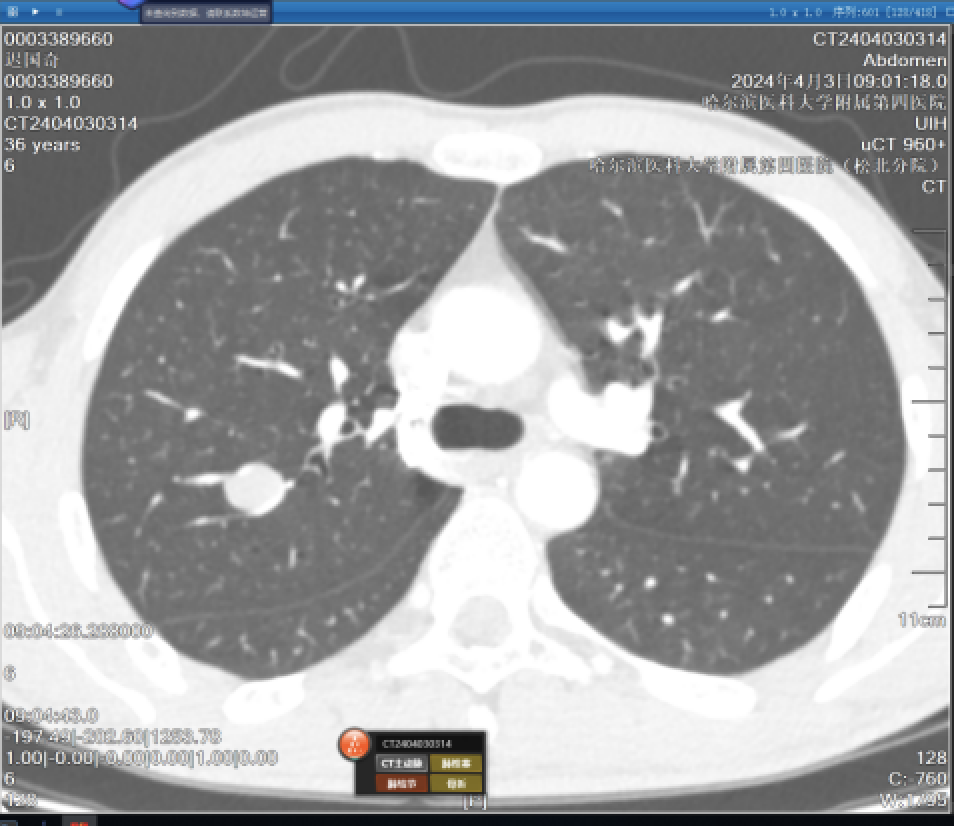

(三)AI智能小结节分析的应用:计算机可以通过自动分割和容积计算方法帮助放射科医生检测到非常小的结节。但AI也会有假阳性、假阴性结果出现,此时就需要放射科医生根据经验来判断AI智能结果是否准确。人脑与智能相结合,使得肺结节的检出更为准确。

图片53.png

图一 AI智能识别肺结节